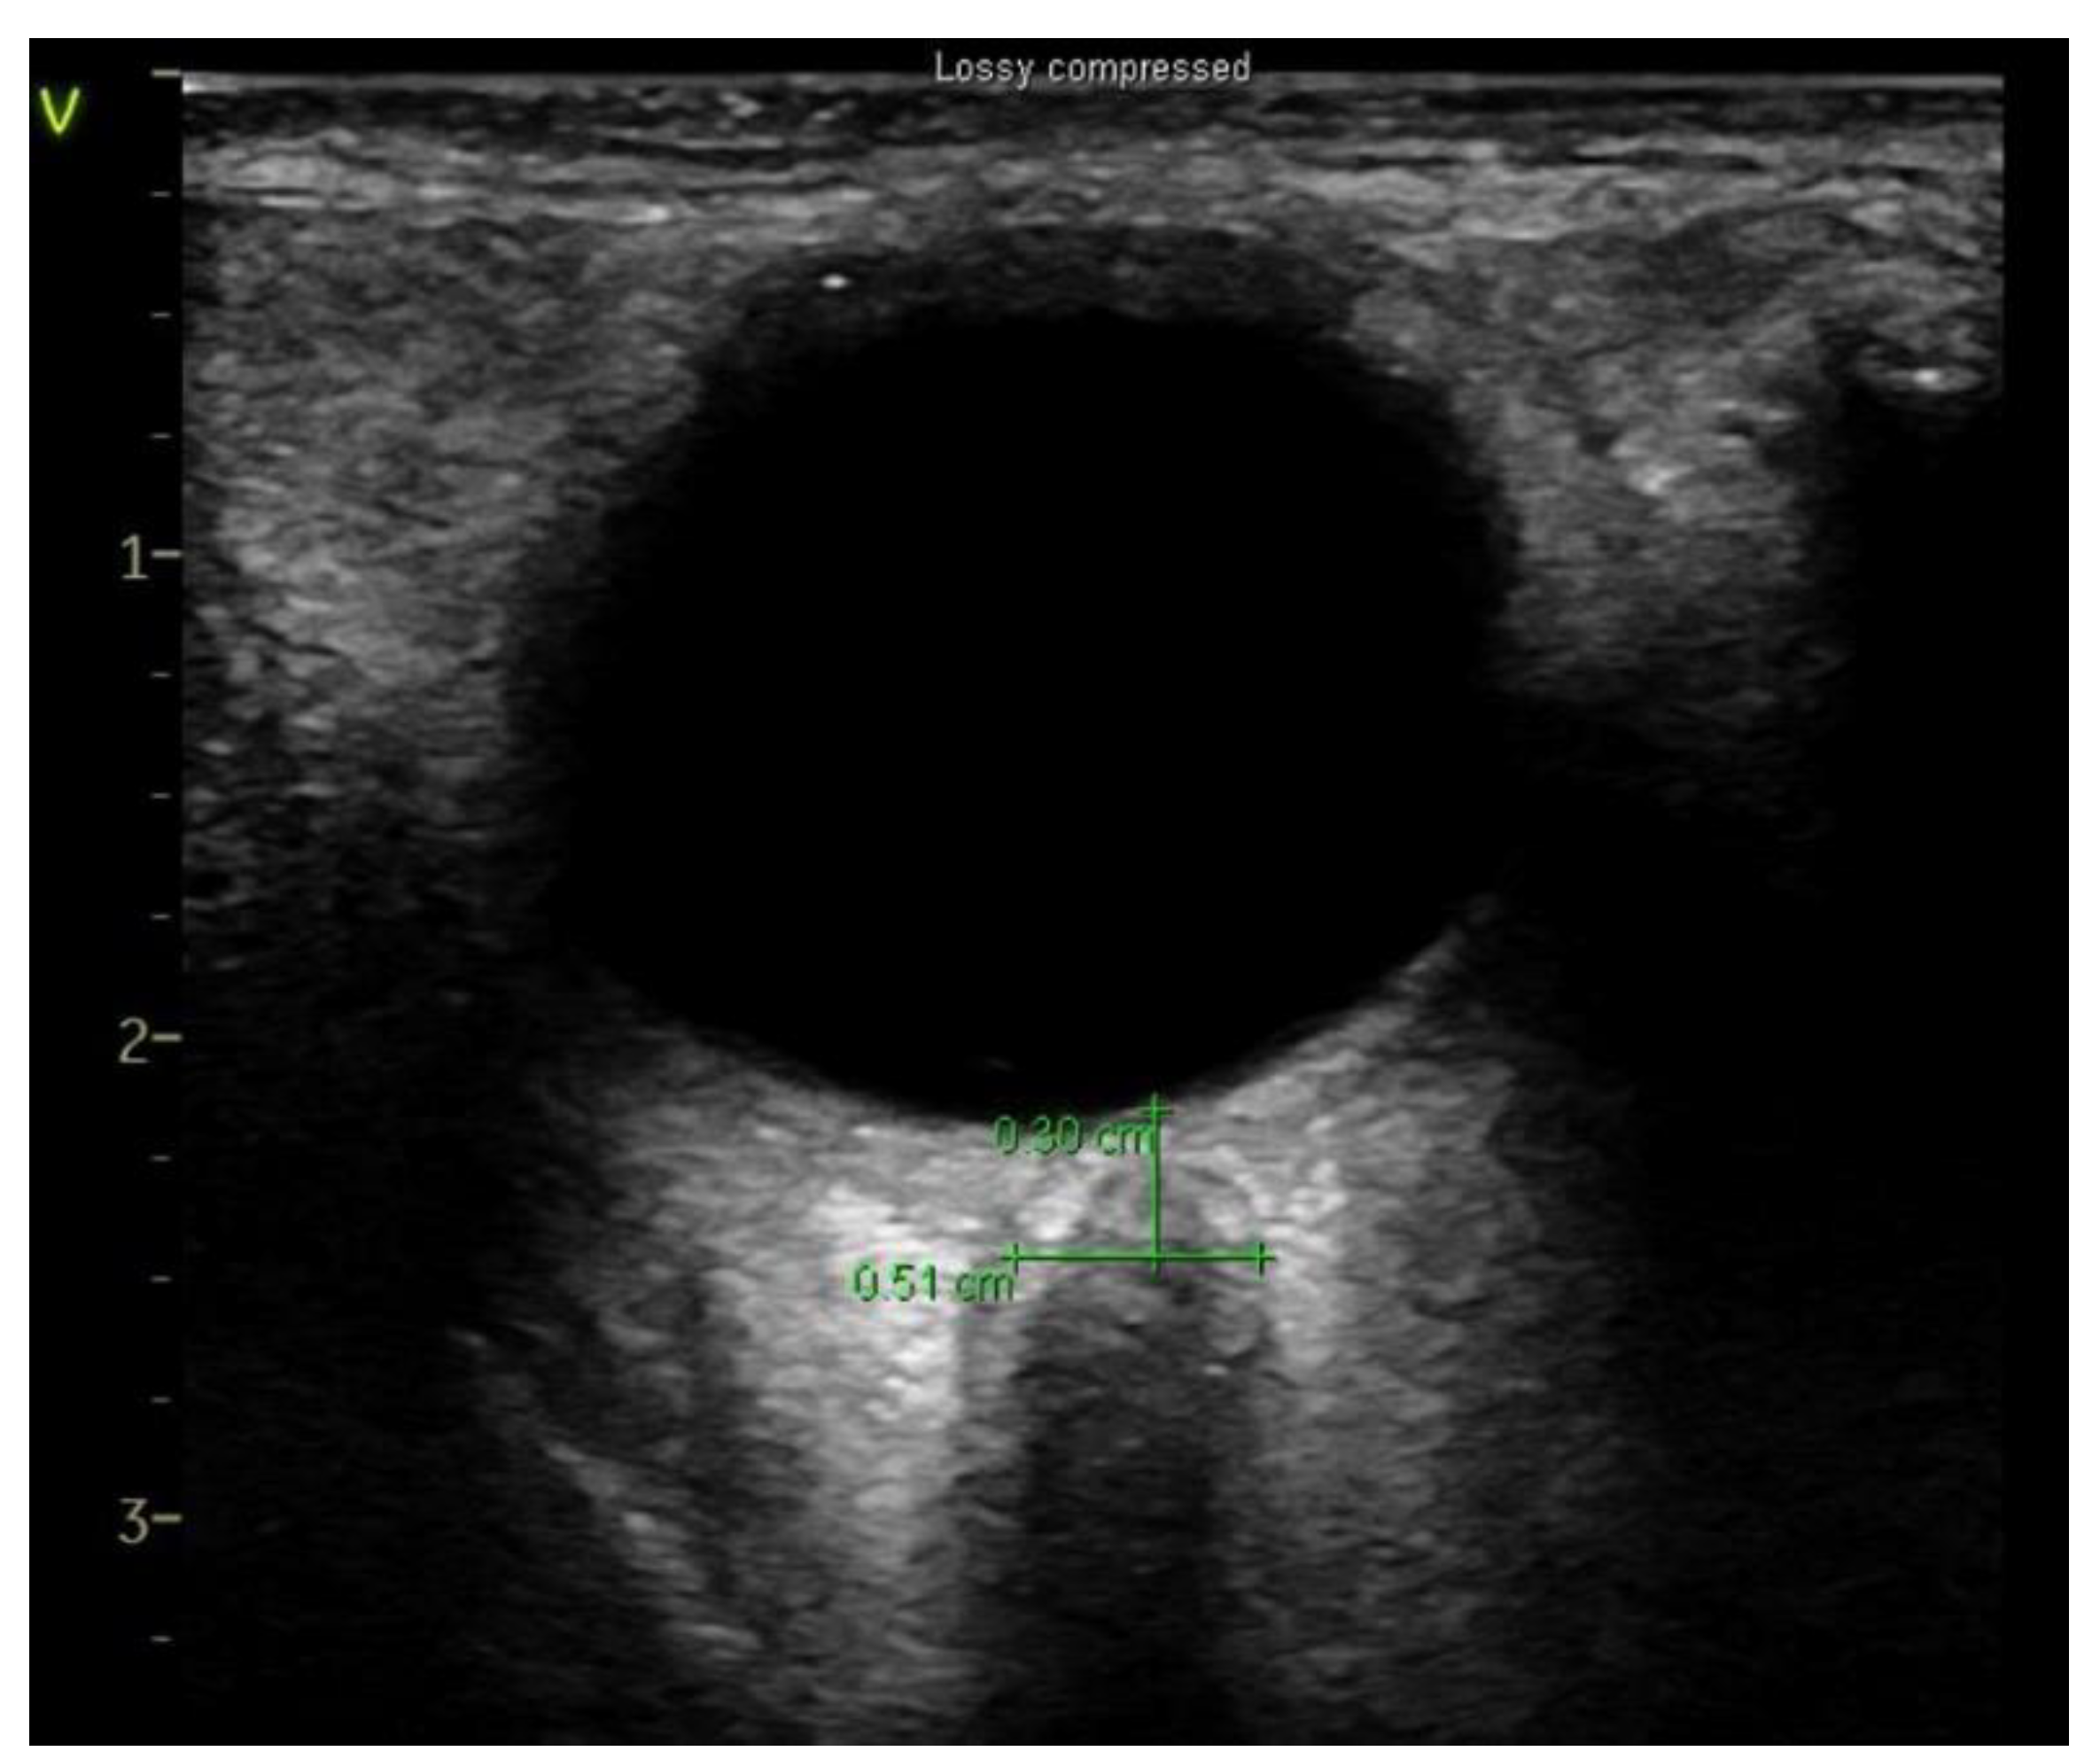

2.3. Ultrasonographic Measurement of Optic Nerve Sheath Diameter